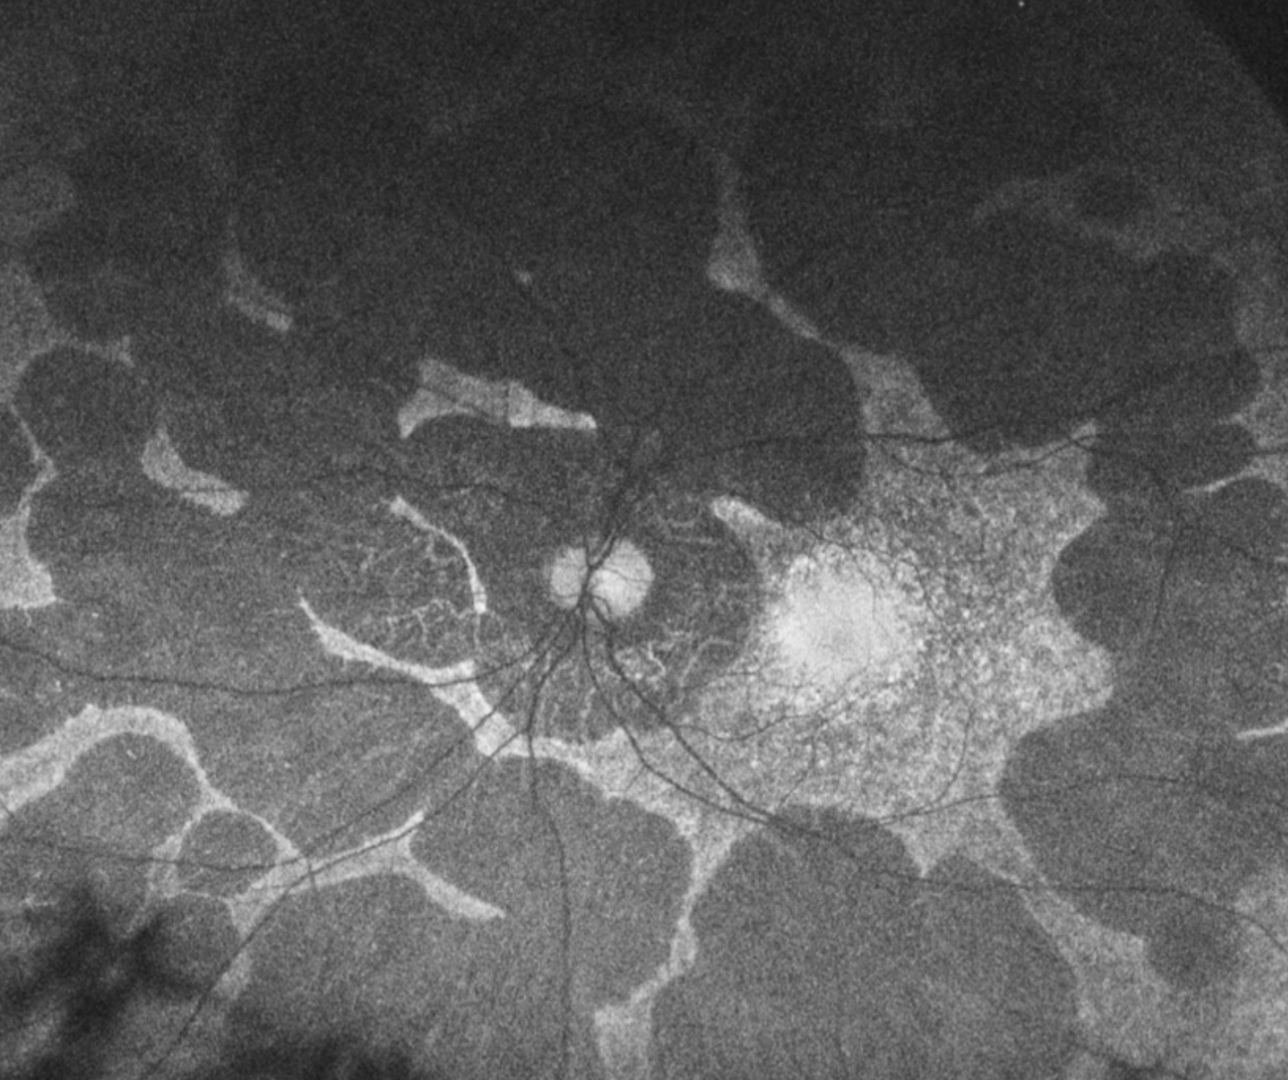

Early in the disease process, patients develop large peripheral areas of chorioretinal atrophy. These areas eventually coalesce forming a scalloped border peripherally, at the junction of the normal and abnormal retina.

The condition is associated with high myopia and astigmatism as well as early cataract formation. Related clinical findings may include macular oedema, choroidal neovascularisation and macular hole formation.

A 30-year-old Caucasian male with best-corrected visual acuity is 6/6 (20/20) in each eye.